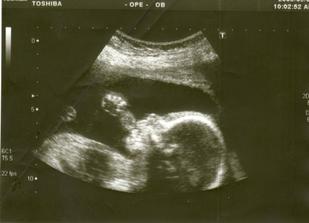

♥ 29.1.2009♥ 1. UTZ - Brouček má 11 mm, jsme 7+2tt a krasně nám bije srdíčko. Tatínek i maminka jsou šťastní a věří v dobrý konec.

♥ 4.2.2009♥ Menší poplach, maminka trošičku špinila, takže neplanovaná kontrola a 2. UTZ. Ale vše je ok, srdíčko krásně tluče a brouček měl otevřenou pusinku 🙂

♥ 3.3.2009♥ Vypadá to, že vše je OK 🙂 Maminka i tatinek jsou šťastný, akorát brouček je trošku lenoch. Vůbec se nechtěl hýbat, jenom mával.

♥ 5.5.2009♥ Velký ultrazvuk - všechno v pohodě a je to KLUK!!!

♥ 7.7.2009♥ Ultrazvuk - vše OK. Akorát jsme pořád hlavičkou nahoru. Ale už jsme hrozně velikýýý 🙂